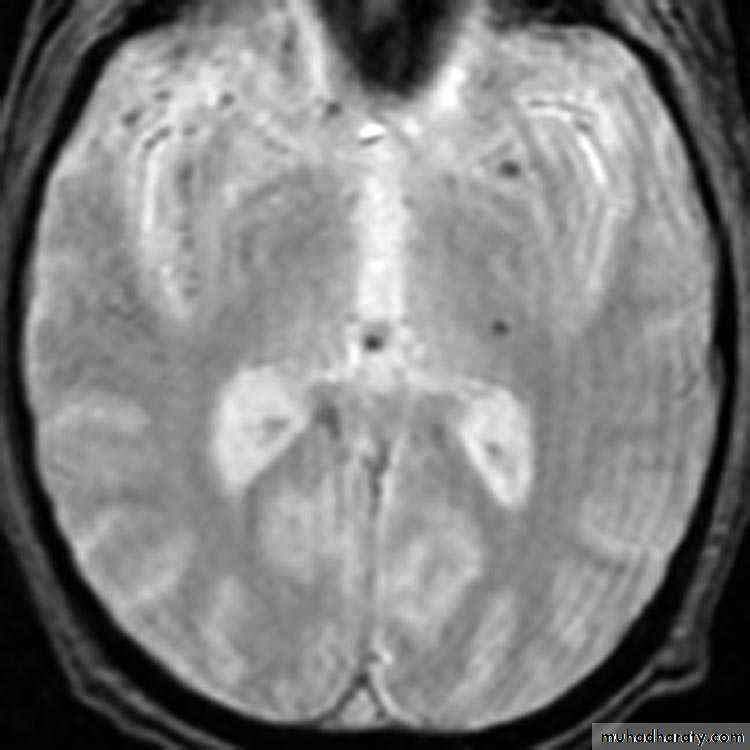

1. Diffuse Axonal Injury

Prolonged post-traumatic state in which there is loss of consciousness from the time of injury that continues beyond 6 hours.

Occurs as a result of mechanical shearing at the grey-white matter interface.

This causes disruption and tearing of axons, myelin sheaths and blood capillaries.

Severity can range from mild damage with confusion to coma and even death.